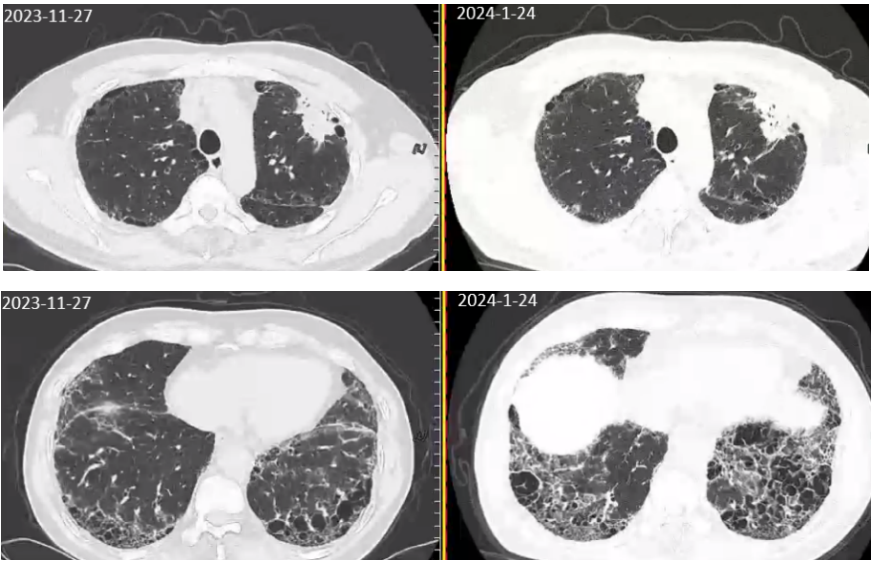

病人手术意愿强烈,经复旦大学附属中山医院会诊后于2023-12-19、2024-01-10接受了2周期新辅助化疗联合免疫(PD-1抑制剂)治疗。2周期治疗后,患者出现进行性加重的呼吸困难,复查胸部CT提示两肺间质性肺炎较前进展(图3),逐渐出现I型呼吸衰竭(动脉血气分析:PaO₂75mmHg(FiO₂70%)。之后2月患者多次于我科RICU住院予呼吸支持治疗,诊断为“间质性肺炎急性加重(AE-IPF)”,予以甲泼尼龙针抗免疫,经验性抗感染治疗后,症状缓解不明显:经鼻高流量湿化氧疗(HFNC,流量55L/min,吸氧浓度70%)下血氧饱和度维持在80%~90%。此时患者因呼吸衰竭无法进行任何的抗肿瘤治疗,且因AE-IPF的发生,命悬一线。

image.png

图3 2周期新辅助化疗联合免疫治疗后复查胸部CT:左上肺肿瘤相仿,间质性肺炎较前进展